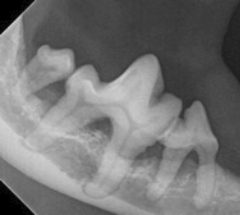

Tenner og tannkjøttet blir undersøkt for skader, feil tannstilling og betennelser. Bakteriebelegg og tannstein blir fjernet fra tennene og under tannkjøttet. Deretter blir tennene polert med en poleringspasta egnet til hund/katt. Digitale tannrøntgenbilder tas.

Behandling går ut på dyp og grundig tann og tannkjøttrens for å bremse utviklingen av sykdommen. Det tas tannrøntgenbilder. Tenner som ikke kan reddes blir trukket. Tann og tannkjøttstatus kartlegges og eieren får veiledning om forebyggende hjemmepleie og om oppfølgingstimer til regelmessig tannkjøttrens. Hvor ofte dyret må ha behandling for denne kroniske sykdommen er veldig individuelt.

Det tas tannrøntgenbilder.

Tannrøntgenbilder tas. Veiledning og informasjon til eieren.

Tannen følges opp med årlig tannrøntgenbilder.

Denne sykdommen er et veldig vanlig tannproblem hos katt og i mindre grad hos hund. Tannen begynner spontant å gå i oppløsning, «resorpsjon». Når resorpsjonen er på krona er tannen veldig vond. Katter med denne sykdom vil ofte endre atferden. For eksempel kan de sikle mer og spise mindre. Tannresorpsjon kan utvikle seg på en eller flere tenner samtidig. Tannrøntgenbilder tas. Basert på nivå av resorpsjon vil tannen ble operert ut eller amputert kirurgisk. Denne sykdommer utvikler seg på flere tenner etterhvert, derfor er det viktig at dyret følges med regelmessig munnhuleundersøkelse, tannrens og tannrøntgenbilder. Informasjon og rapport til eieren.